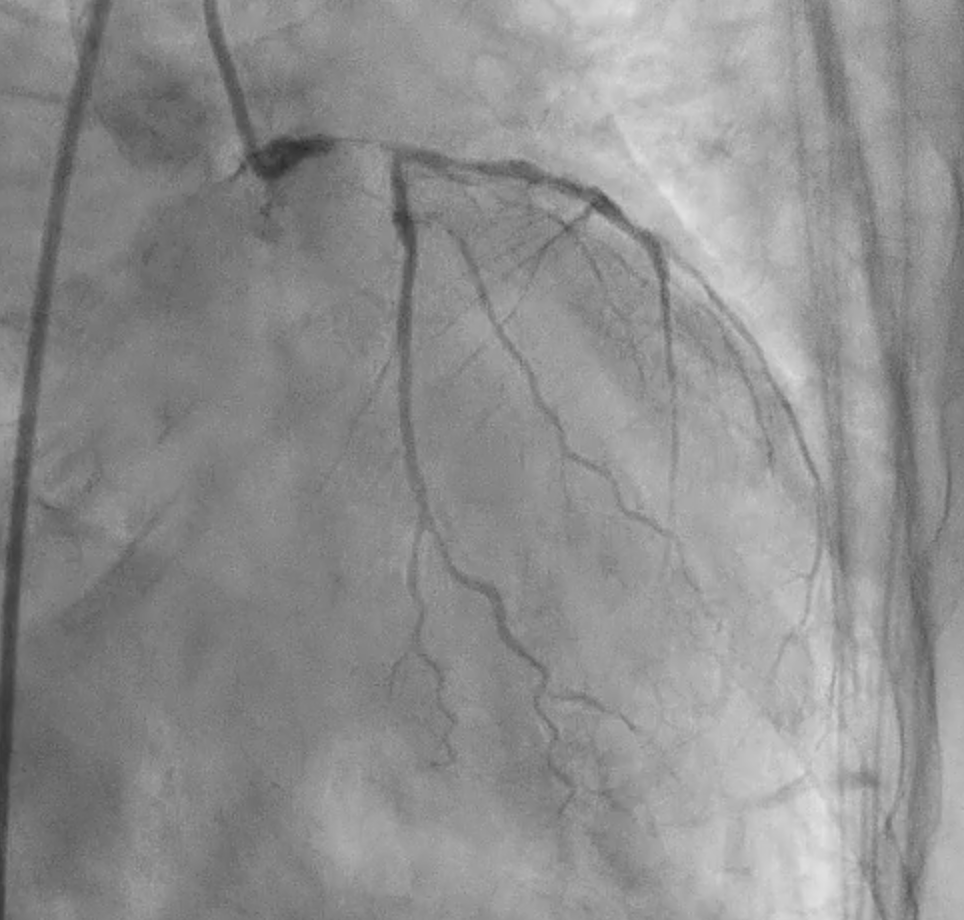

Under IABP (left femoral), PCI via right brachial with 6 Fr EBU 3.5. Runthrough to LAD, Sion Blue to LCX. Predilation of LM/pLAD with 2.0¡¿20 mm balloon; IVUS pullbacks. Further dilatation with 2.5¡¿20 mm NC for mLAD underexpansion, pLAD, and LM. oLCX de novo and pLCX edge ISR predilated with 2.5¡¿20 mm NC; LCX ISR treated with DCB 2.5¡¿20 mm. Szabo technique attempted for LM–LAD with a 3.0¡¿24 mm DES; the undeployed stent dislodged during repositioning and was deployed at the dislodgement site. IVUS showed 2–3 struts protruding into the aorta from the LM ostium and incomplete pLAD coverage. Post-dilation with 3.5¡¿20 and 2.5¡¿20 mm NC; DCB 3.0¡¿20 mm for pLAD uncovered plaque and mLAD proximal edge ISR. Final CAG: TIMI 3 flow.At 3 months, staged PCI via right radial with 6 Fr EBU 3.5. Sion Blue ES to distal LAD. IVUS: mLAD stent underexpansion (MSA <2.0 mm©÷); wire not through struts. IVL 3.5¡¿12 mm initially could not cross LM; after guide exchange (JL 3.5, then EBU 3.0/3.5), IVL advanced to mLAD and delivered 100 shocks, producing a ring crack and area gain. Further dilation with 3.0¡¿20 and 3.5¡¿20 mm NC. IVUS: pLAD type B dissection without flow limitation. DCB 3.5¡¿40 mm to p–mLAD. LM ostial stent further dilated with 3.5¡¿20 mm. Final CAG: TIMI 3 flow.